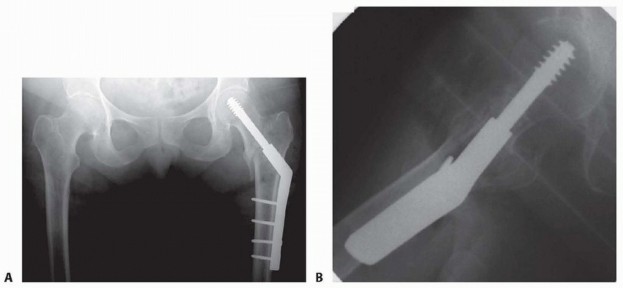

Peritrochanteric hip fractures are defined as extracapsular hip fractures, always involving the trochanter and frequently with extension into the subtrochanteric region. Medicare data indicates that as management of osteoporosis has improved, individual risk of sustaining a hip fracture has declined. 4 However, with an aging population, the total number of hip fractures increases each year. According to a Medicare database, 786,717 hip fractures were reported between 1986 and 2005. These fractures account for approximately 20% of Medicare claims. These fractures require operative intervention to achieve stable fracture fixation to allow immediate patient mobilization. ## ANATOMY The intertrochanteric region of the hip is notable for the anatomic transition from the femoral neck to the femoral shaft. The angle subtended by the femoral neck and long axis of the femoral shaft in the coronal plane (the neck-shaft angle) is usually between 120 and 135 degrees in adults. Studies have shown that this angle tends to decrease slightly with age. The average femoral neck is anteverted between 10 and 15 degrees with respect to the femoral shaft. 15 The peritrochanteric region of the femur is composed of multiple thickenings of trabecular bone distributed in compressive and tensile groups.5 The thickest and most structural are the primary compressive trabeculae located along the posterior medial aspect of the femoral neck and shaft, also known as the calcar. Multiple muscle groups attach to this region of the femur: Iliopsoas: attaches to the lesser trochanter and exerts a flexion and external rotation force to the hip Abductors and short external rotators: attach to the greater trochanter Adductors: attach to the femoral shaft distal to the peritrochanteric region The blood supply to the peritrochanteric region of the femur is rich and abundant. The medial and lateral femoral circumflex arteries supply the cancellous bone of the trochanteric region through muscle attachments at the vastus origin and the insertion of the gluteus medius. ## PATHOGENESIS In the elderly population, most peritrochanteric fractures are caused by a fall onto the lateral aspect of the hi Numerous factors, such as structurally weak bone, lack of subcutaneous padding, and slowed protective reflexes lead to increased risk of hip fracture in the elderly population. Pathologic lesions in the peritrochanteric region are not uncommon and may lead to fractures after relatively minor trauma. Young patients who sustain peritrochanteric fractures are typically victims of high-energy trauma. In these cases, the fracture must be approached differently, with an attitude toward anatomic restoration of joint mechanics. ## NATURAL HISTORY Almost all peritrochanteric hip fractures will heal without intervention. However, owing to the pull of the musculature in this region, the fracture will heal in gross malalignment, leading to subsequent functional limitations. 17 Early operative intervention of these fractures is undertaken to restore anatomic alignment and ensure that patients are mobilized quickly. Early fixation has been demonstrated to decrease incidence of pressure sores, pneumonia, and 30-day mortality. ## PATIENT HISTORY AND PHYSICAL FINDINGS It is important to elicit the cause of the patient's fall, as many falls in the elderly population that result in hip fractures are due to medical comorbidities. Elderly patients should be carefully evaluated and treated for rhabdomyolysis, dehydration, urinary tract infection, and malnutrition. In cases of preexisting poor mobility, consider deep vein thrombosis, and in anticoagulated patients it may be appropriate to obtain brain imaging. Complaints of hip pain before falling may indicate a preexisting pathologic process that requires further evaluation. A thorough whole-body musculoskeletal examination of the patient is necessary because of the high incidence of associated fractures (especially of the wrist and proximal humerus) in the elderly population sustaining hip fractures from simple falls. In cases of visible head trauma, cervical spine imaging can obviate prolonged cervical collar immobilization. Examination of the soft tissue overlying the lateral hip, sacrum, and heels is necessary to ensure that no pressure ulcers or abrasions have occurred in these areas. The classic physical finding in a patient with a peritrochanteric hip fracture is a shortened, externally rotated lower extremity. Passive logrolling of the leg will elicit pain. This may be an especially helpful finding in occult hip fractures with no obvious fracture deformity. 403 ## IMAGING AND OTHER DIAGNOSTIC STUDIES Plain radiographic anteroposterior (AP) pelvis and cross-table lateral images of the injured hip should be obtained initially. AP and lateral views of the femur, including the knee joint, should be obtained both to assess the femoral bow as well as to evaluate the femoral canal in the event that an intramedullary device is required. A traction radiograph (radiograph taken with firm manual traction and internal rotation of the leg) will provide more information on the fracture pattern and will allow a better comparison to the uninjured hip ( FIG 1A,B). Alternatively, an obturator oblique view of the pelvis can allow for this comparison without requiring additional analgesic medication. A fine-cut (2 mm) computed tomography (CT) scan with reconstruction images (sagittal and coronal) set to bone windows may help assess the fracture when ipsilateral femoral neck or other fractures are suspected. Magnetic resonance imaging (MRI) is the modality of choice to assess for the presence of an occult peritrochanteric hip fracture in the setting of significant hip pain and normal radiographs ( FIG 1C).

### FIG 1 • A. AP radiograph of an AO/OTA type 31-A1 pertrochanteric hip fracture. B. Traction radiograph; note the reduction seen with traction. C. MRI scan of a painful right hip showing an occult peritrochanteric fracture (arrow) not seen on plain radiographs. D. Lateral radiograph of an AO/OTA type 31-A3 intertrochanteric fracture. Note the displacement of this high-energy fracture, occurring in a young patient.